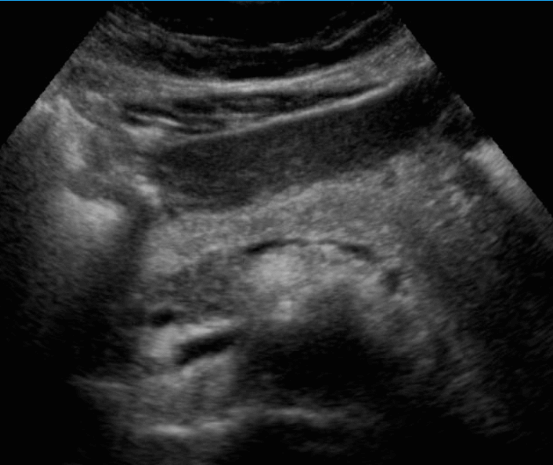

정상췌장의 초음파적 소견

췌장은 막이 없는 장기로 초음파상 경계면이 확실하지 않다. 췌장의 에코는 간보다 약간 밝거나 같으며 균질하다. 나이가 증가하면서 위축되고 지방침착으로 인해 췌장 실질이 밝아진다. 주췌관의 직경은 3mm 이상이면 확장으로 보나 분단위로 수축과 확장을 반복하여 변하기 때문에 시간에 따라 확인해야 한다. 실제검사에서 대칭성의 소실, 외곽선의 급격한 변화, 에코변화등을 주의 깊게 관찰해야 한다.

- 돌출 없는 매끈한 모양의 실질, 두께 4cm 이하

- 간실질보다 조금 높은 균질한 에코

- 균일한 직경의 2mm 미만 췌관

- 예리한 모양의 구상돌기

- 주위정맥들의 눌림이 없다

- 췌장주위 비정상 액체저류가 없다

- 길이 12cm

- 두께 head 2.5cm (2.5cm 이상이면 종대), body 2cm (2cm 이상이면 종대), tail 1.5~2cm (2cm 이상이면 종대)